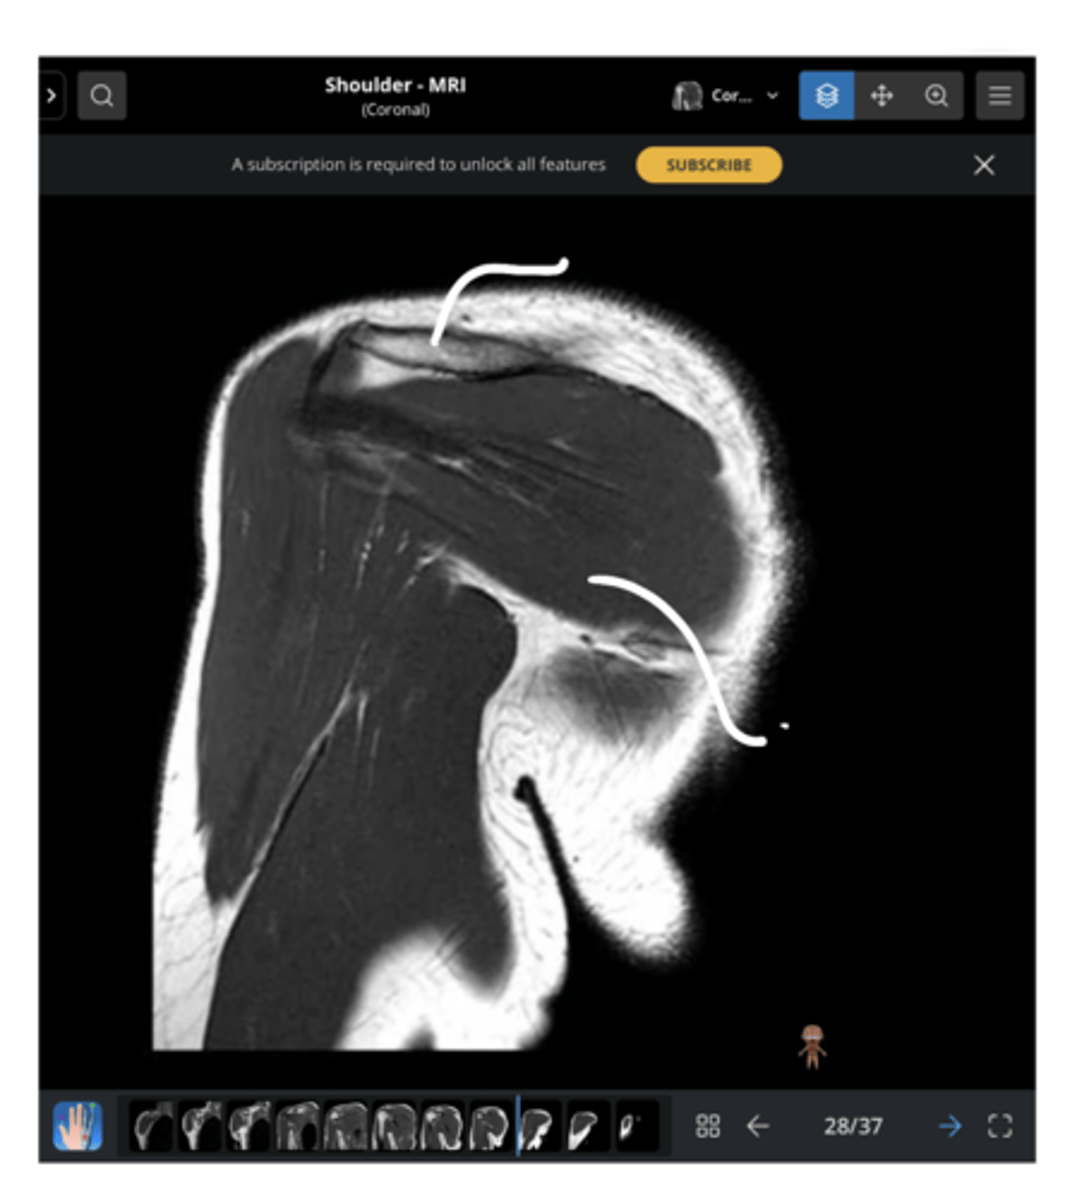

Posterior coronal view of the shoulder -- now, instead of seeing the supraspinatus, we are seeing the infraspinatus

What type of view is this? Anterior vs. posterior? How do you know?

1. Posterior coronal view

2. NO CORACOID

3. Posterior deltoid

1. What view is this image?

2. How do you know?

3. Which structure is being pointed to?

2. NO CORACOID -- spine of the scapula

3. Superior = spine of the scapula, inferior = infraspinatus

3. Which structures are being pointed to?

2. Glenoid